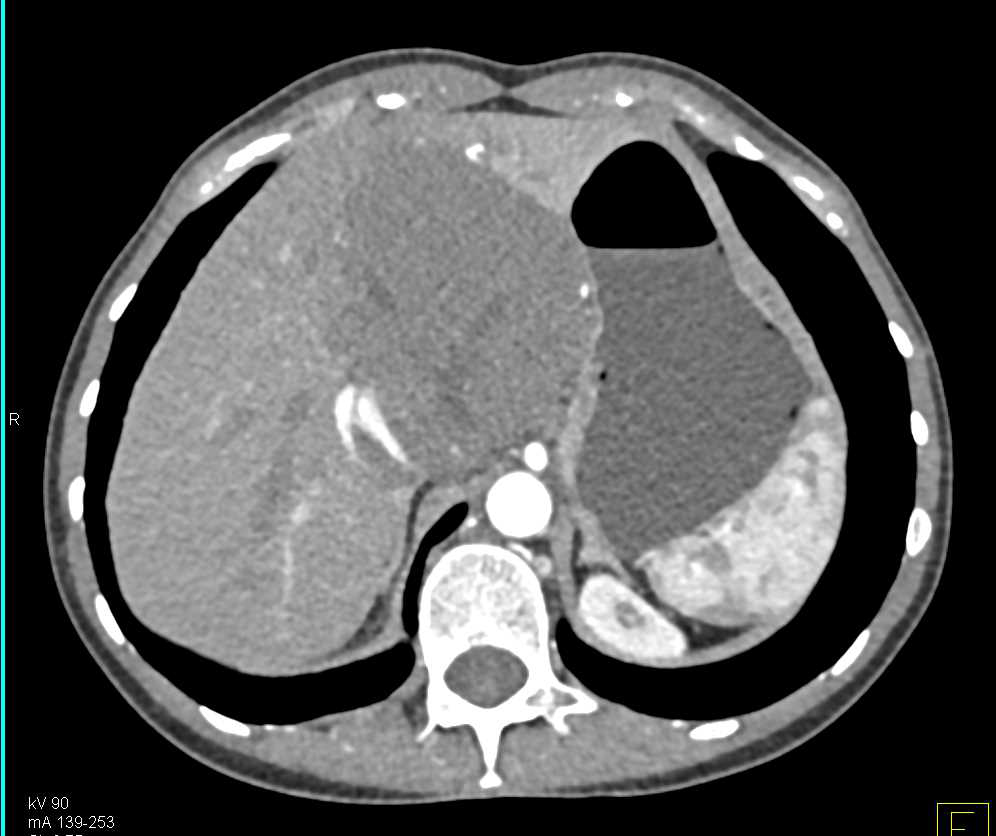

Hemangioma Liver